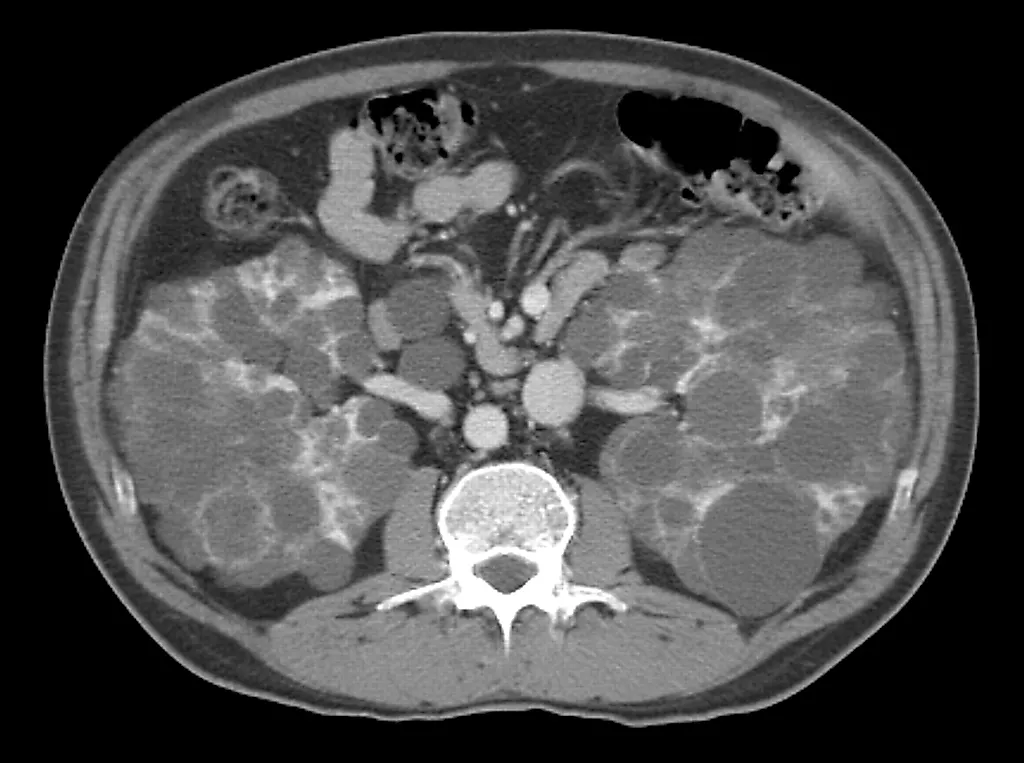

Помогает отличить тканевые образования от жидкостных и позволяет диагностировать простую кисту почки Этот метод также поэволяет поставить диагноз при ангиомиолипоме на основании характерного усиления эхогенности за счет жировой ткани.   является единственным наиболее информативным радиографическим тестом, позволяющим определить характер объемного образования. КТ с введением и без введения контрастного вещества обладает преимуществом при исследовании хорошо васкуляризованных паренхиматозных опухолей.

Тканевые образования с участками отрицательных значений затухания по шкале КТ (единицы Хунсфилда) указывают на наличие жировых включений, характерных для ангиомиолипомы. Примерно в 10 % случаев КТ не позволяет выполнить дифференциальную диагностику объемного образования, что диктует необходимость проведения дополнительных диагностических мероприятий или хирургического вмешательства с целью ревизии почки.   не обладает преимуществами по сравнению с КТ или ультразвуковым исследованием при дифференциальной диагностике объемного образования почки. В связи с тем, что КТ и ультразвуковое исследование являются менее дорогими и более доступными, применять МРИ для первичной диагностики объемных образований почек не рекомендуется.

Сложная киста почки имеет один или несколько признаков, которые могут быть характерны для злокачественного новообразования, например внутренние перегородки, кальцификаты в стенках кисты и внутренних перегородках, высокую плотность или неоднородность внутреннего содержимого кисты, неровные края или участки усиления контрастности при КТ. Сложные кисты с перегородками и кальцификатами в большинстве случаев являются доброкачественными образованиями, тогда как другие перечисленные признаки более характерны для почечно-клеточного рака.

Если объемное образование выявлено при внутривенной урографии, следующим этапом является проведение ультразвукового сканирования В том случае, когда при этом определяется простая киста почки, дальнейшее обследование не требуется Обнаружение жировых включений в тканевом образовании при ультразвуковом ис-сдедовании свидетельствует о наличии ангиомиолипомы Определение других тка невых или сложных кистозных образований является показанием к проведению КТ Контрастное усиление тканевого образования при КТ подтверждает наличие почеч-но-клеточного рака, однако примерно 10 % таких образований могут оказаться доброкачественными (онкоцитома и аденома). При невозможности поставить диагноз при КТ требуется выполнение артериографии или перкутанной биопсии Такой подход позволяет поставить диагноз у большинства пациентов.